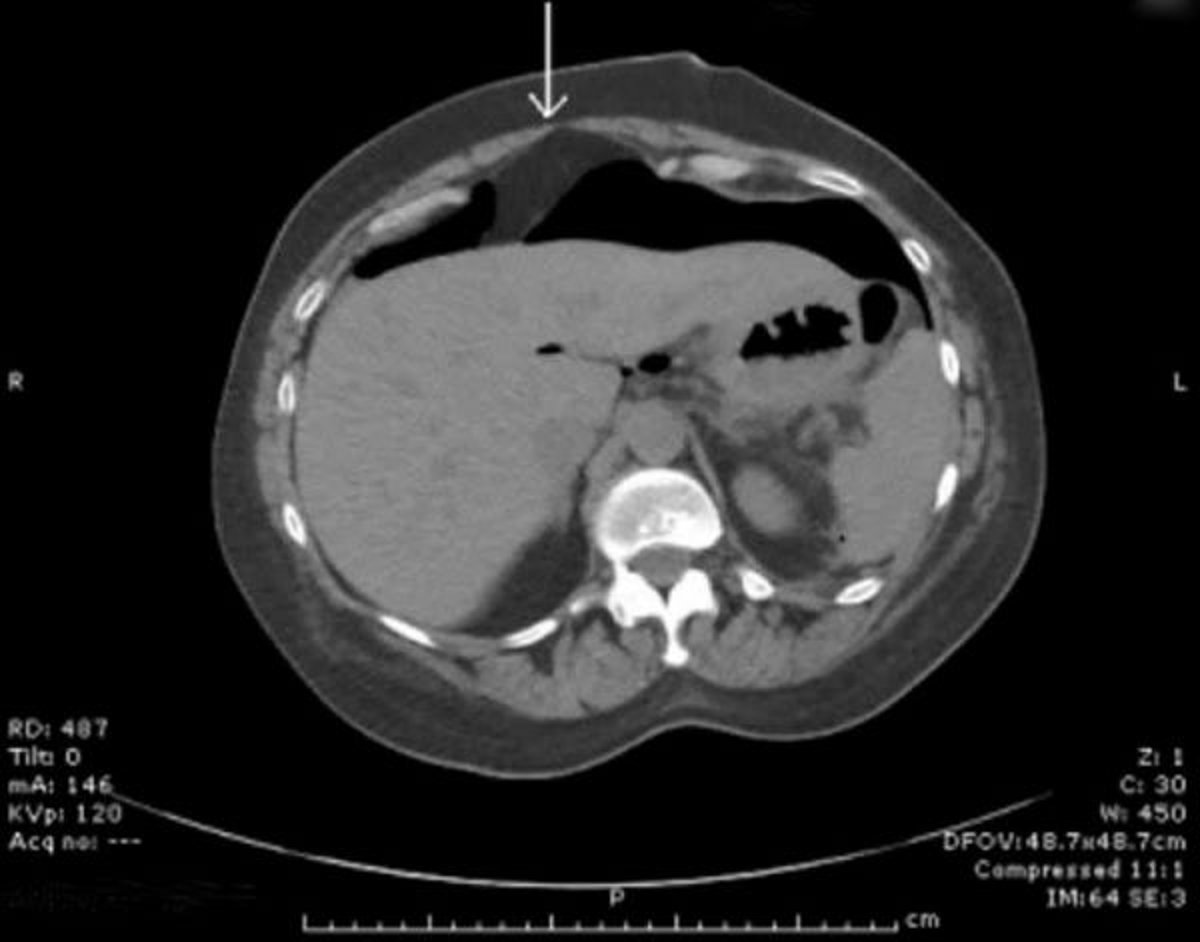

腹腔内遊離ガス像を示したCT画像

肝臓の前方に遊離ガスを認める。矢印は肝鎌状間膜を示している。

Image provided by Parswa Ansari, MD.